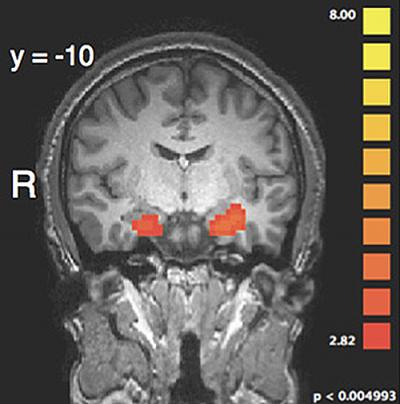

The fMRI scans revealed the areas of the brain that are involved in this complex process. They found that the amygdala, an almond-shaped set of neurons that plays a key role in processing emotions, responded most strongly to the graphic language condition. Like the punishment ratings themselves, however, this effect in the amygdala was only present when harm was done intentionally. Moreover, in this situation the researchers found that the amygdala showed stronger communication with the dorsolateral prefrontal cortex (dlPFC), an area that is critical for punishment decision-making. When the harm was done unintentionally, however, a different regulatory network – one involved in decoding the mental states of other people – became more active and appeared to suppress amygdala responses to the graphic language, thereby preventing the amygdala from affecting decision-making areas in dlPFC.